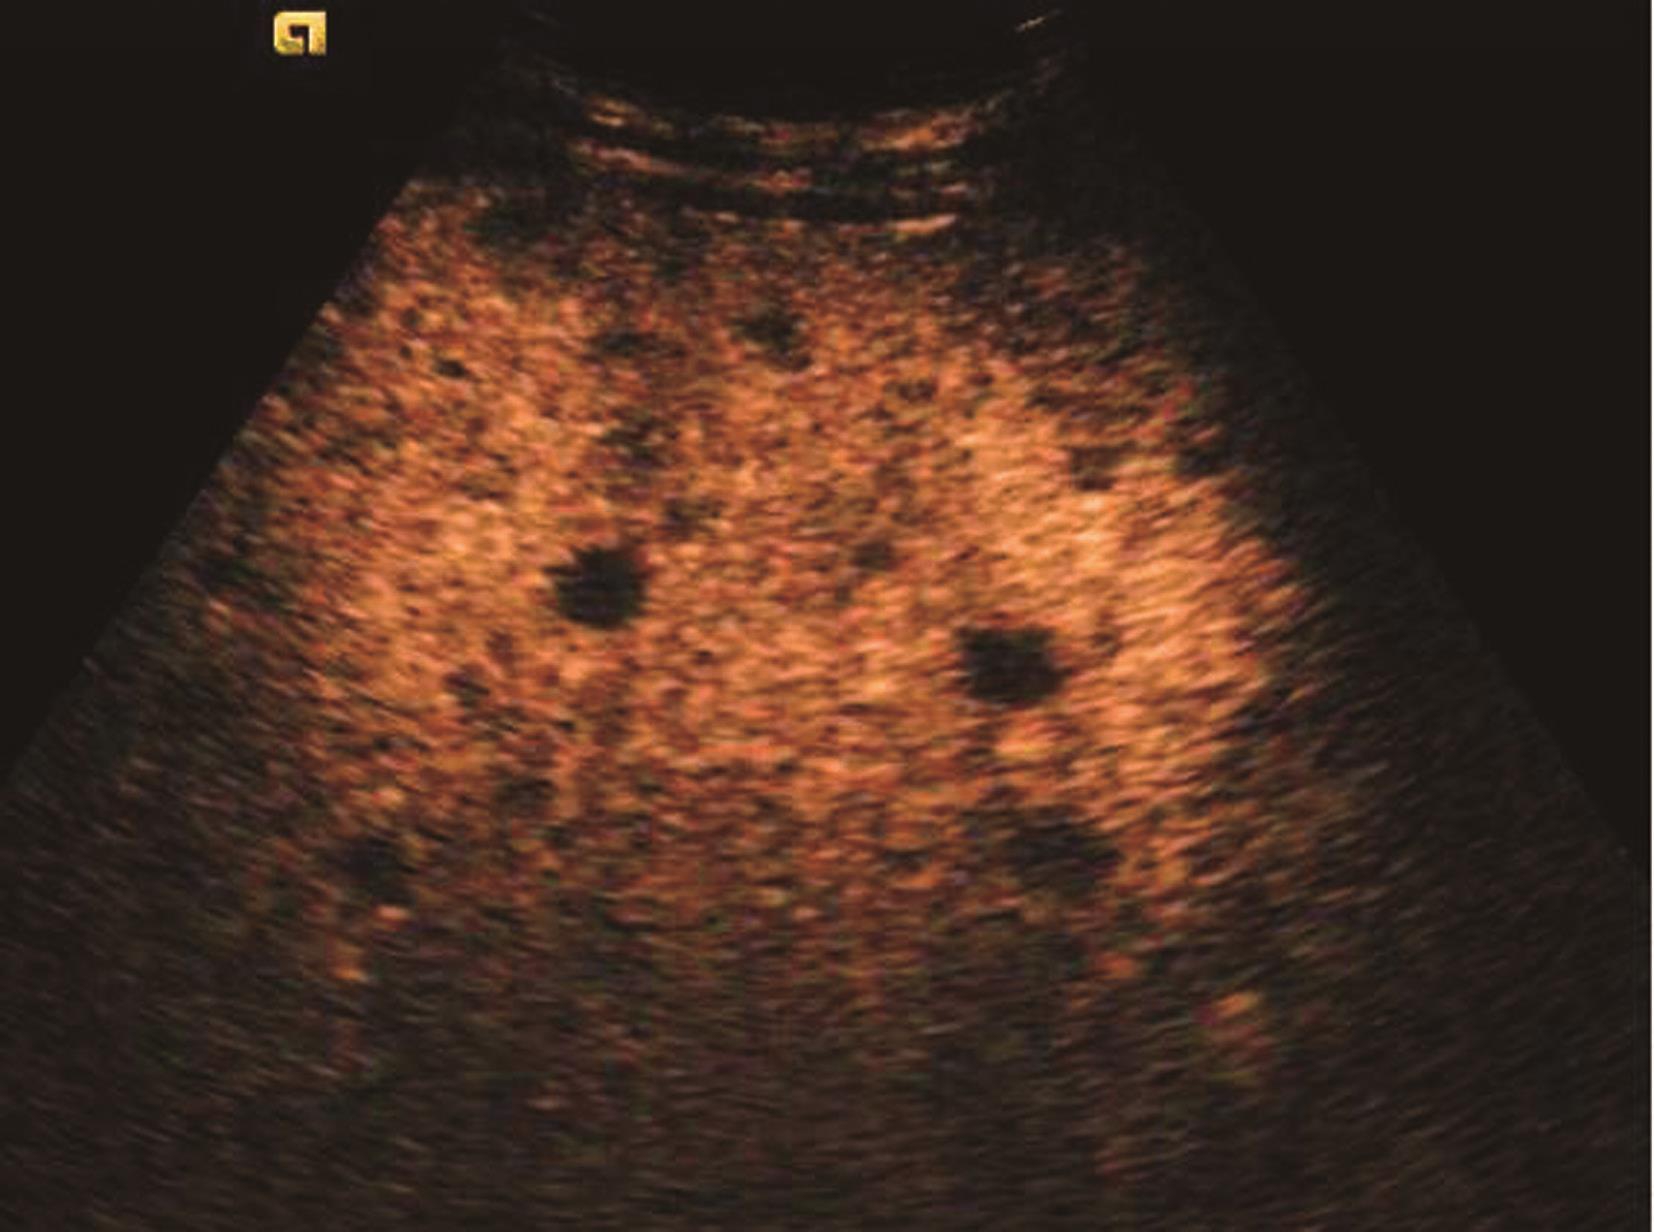

发生在肝外的恶性肿瘤,通过血行播散或淋巴管转移至肝脏,为肝脏最常见的恶性肿瘤之一,多表现为累及全肝的大小不等的多发性结节,少数病例为弥漫性或为单发结节,病理形态与原发癌相似,较大肿块常伴变性坏死。

①“牛眼征”或“靶形”结节:即癌结节周边有较宽的低回声晕环;内部为较均匀的高回声或等回声;高回声中央部有小片状无回声区或低回声区,为出血或坏死所致。“牛眼征”被认为是转移性肝癌的典型声像图特征。此型可出现于任何转移性肝癌,但多见腺癌肝转移。②高回声型:癌肿边界清楚,形态欠规则,内部回声显著高于周围肝组织,甚至伴有钙化,后方回声可有衰减。各部位恶性肿瘤肝转移常表现为高回声型。③混合型:癌肿边界清楚,形态较规则。内部以高回声或等回声为主,近癌肿中心区因组织坏死出现范围较大的不规则无回声区。鳞癌肝转移有发生中心坏死的倾向。④低回声型:圆形、椭圆形或稍不规则形,癌肿边界清楚,可向周围组织伪足样生长,直径常小于3cm,内部呈低回声,与低回声型原发性肝癌相似,可见于各种肿瘤的肝转移。⑤无回声型:较少见,圆形、椭圆形或稍不规则形,癌肿边界清楚,内部可见稀疏的微弱回声,增大增益可出现微弱回声,后方回声增强,多见于淋巴瘤、乳腺癌、胰腺癌、卵巢癌、黑色素瘤及肉瘤等疾病。癌肿大部分溶解坏死时声像图表现酷似肝囊肿,但病灶边界多不规则,且常为多房性,其隔膜回声呈不规则增厚,少数肿瘤内壁有乳头状突起。⑥周围组织的继发征象:转移性肝癌罕见有门静脉、肝静脉或下腔静脉癌栓出现,此点与原发性肝癌易向门静脉播散的特点不同。此外,转移癌肿不断增大时,可发生与原发性肝癌类似的肝内肝外挤压征象。转移性肝癌二维灰阶图像如图5-21-22所示。

图5-21-22 多发性肝转移癌二维灰阶图像